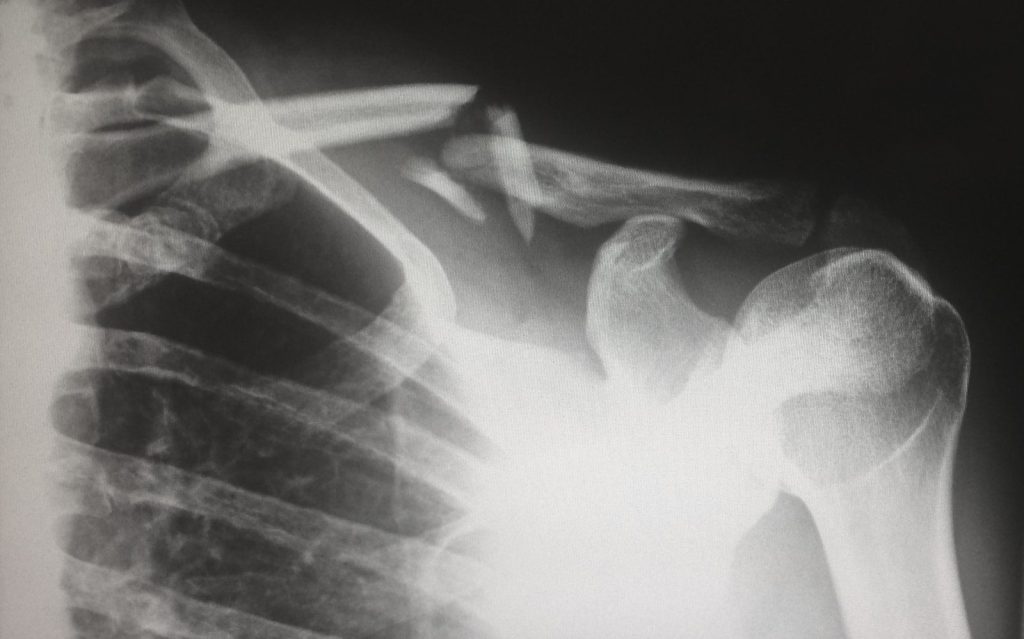

Radiographie conventionnelle

La base. Rayons X, os, poumons, abdomen. Rapide, universelle, encore massivement utilisée. C’est la première chose qu’on apprend et la dernière qu’on arrête de faire.

Coupes millimétrées de tout le corps, reconstructions 3D. Urgences, oncologie, traumatologie. Le cheval de bataille des CHU marocains. Irradiant mais rapide et précis.